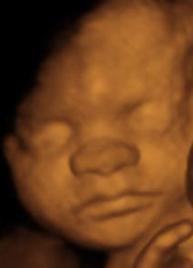

Evite el uso de cremas hidratantes y aceites sobre la piel del abdomen desde cinco antes de la ecografía.

En caso necesario, si el bebé está de espaldas y se mueve poco, puede tomar un zumo de fruta, tomar una chocolatina que favorezcan el cambio de postura y así poder ver la parte delantera. No acuda nunca en ayunas.